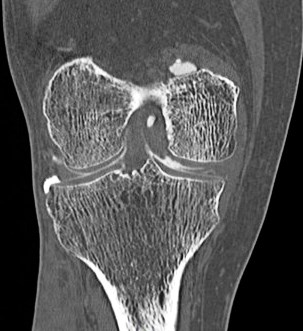

68 yo male with medial knee pain and a pacemaker.

Figure 1 for case Medial meniscus tear ( RID2772 )

Figure 1

Oblique tear of the medial meniscus shown on a CT arthrogram.

Medial meniscus tear ( RID2772 )